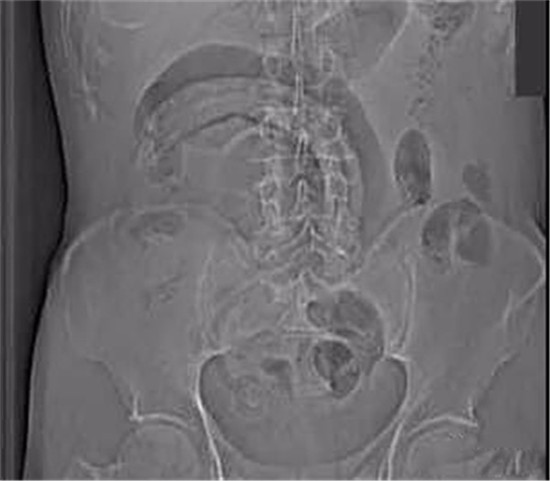

医生给他检查的时候,发现已经有腹膜炎症状,怀疑肠梗阻,拍了个片子,就是上面那个片子:一条大黄鳝在肚子里。

上面是前几年一名患者大肠里的黄鳝。

这条黄鳝还是雌性的黄鳝,你知道我怎么看出来的吗?